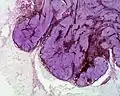

Cellular blue nevus Epithelioid blue nevus